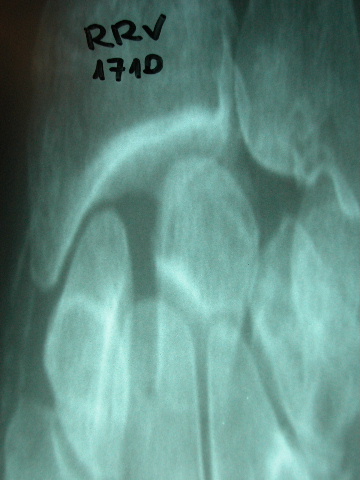

Fractura de cuello de fémur.

Fractura de fémur, prótesis parcial de cadera

Fractura de cuello de fémur

Fractura de cuello de fémur con tornillos de tracción